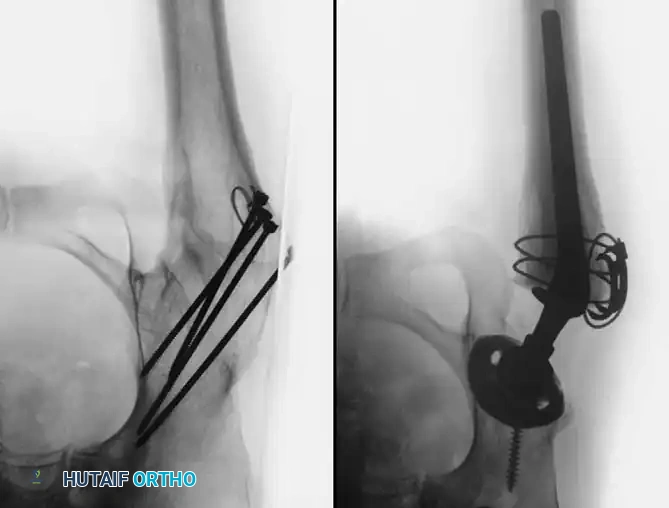

Principles of Reconstruction

The surgical management of protrusio acetabuli is technically demanding and relies on three non-negotiable biomechanical principles:

1. Restoration of the Anatomic Hip Center: The hip center of rotation must be lateralized and brought inferiorly to its true anatomic position to restore abductor mechanics and minimize joint reactive forces.

2. Peripheral Rim Fixation: The implant must be supported by the intact, structurally sound peripheral rim of the acetabulum, bypassing the deficient medial wall.

3. Medial Wall Reconstruction: Cavitary and segmental defects of the medial wall must be reconstituted, typically utilizing impaction bone grafting (autograft from the resected femoral head or allograft).

Fig. 7-75 Reconstruction for protrusio acetabuli deformity. A, Diagrammatic representation of medial wall grafting and lateralized cup placement.

Fig. 7-75 Reconstruction for protrusio acetabuli deformity. B, After total hip arthroplasty. Hip center was restored to more lateral and inferior position. Large acetabular component allowed rim fixation without need for screws, and medial deficits were grafted with cancellous autograft from femoral head with excellent incorporation.

Surgical Technique